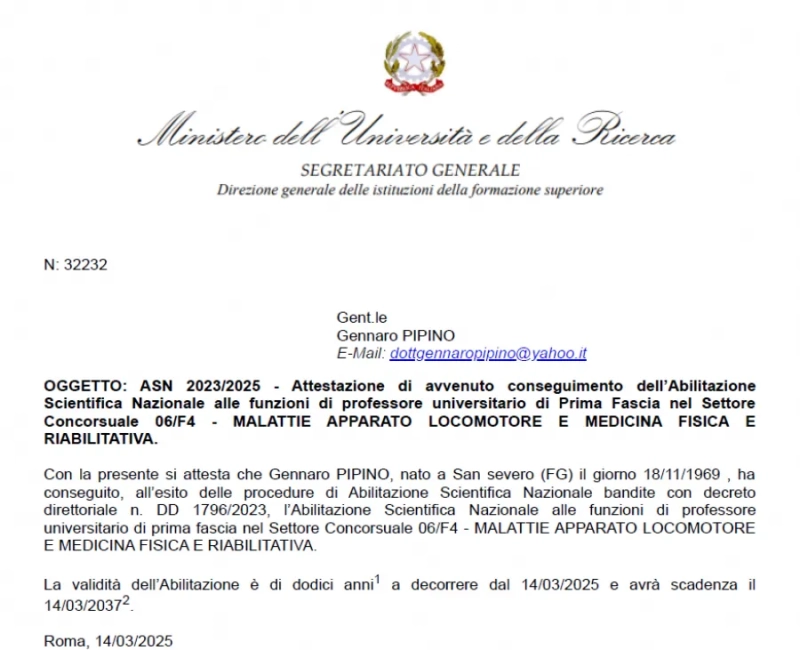

Prof. Pipino Gennaro, outsider a livello internazionale nella Chirurgia protesica di ginocchio mediante sistemi digitali ed intelligenza artificiale nel rispetto degli assi meccanici ed il ripristino totale della anatomia e cinematica del ginocchio protesizzato.

- Responsabile dell’Unità Operativa Ortopedia III presso Casa di Cura Villa Erbosa di Bologna;

- Professore a contratto della Scuola di Specializzazione in Ortopedia e Traumatologia presso l’Università Vita - Salute San Raffaele di Milano;

- Progettista di sistemi innovativi protesici mini-invasivi per ortopedia;

- Responsabile mondiale del primo studio per trapianti di cartilagine con azienda statunitense OLIGOMEDIC per il trapianto Joint REP;

- Progettista e titolare del brevetto dell’allineatore Trans Epicondilare per chirurgia protesica di ginocchio.